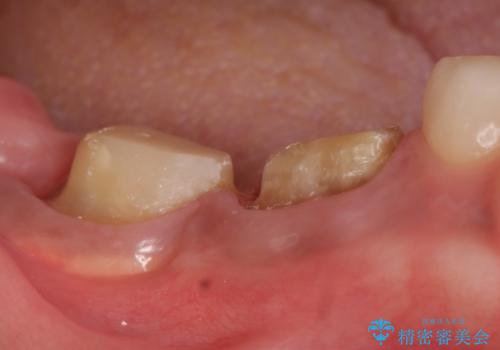

- 奥歯が欠けてしまったので診て欲しいといらっしゃった方の症例です。

再根管治療終了後、オールセラミッククラウンによる補綴を行いました。